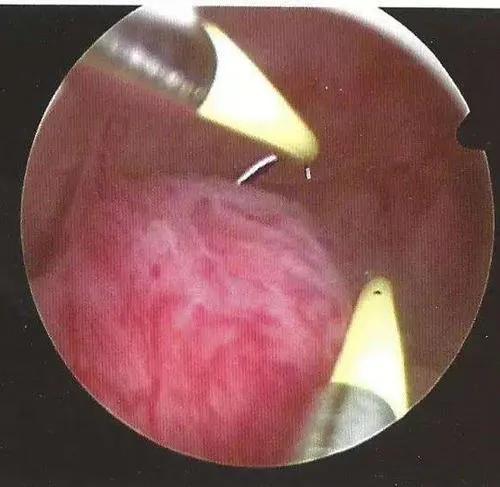

宫腔镜则是绝经后子宫内膜息肉的诊断金标准,可直视宫腔全貌,观察子宫内膜息肉形态以及表面血管情况,初步判断是否存在恶变。宫腔镜诊断子宫内膜息肉的准确率达93.8%,尤其对于多发性子宫内膜息肉,诊断准确率可高达 98.0%。

对于子宫内膜息肉,宫腔镜下有两种手术方式:子宫内膜息肉摘除术和子宫内膜息肉电切术。

子宫内膜息肉电切术是一种微创治疗方法,也是子宫内膜息肉首选的手术方式。由于子宫内膜较薄,该术式可仅从蒂部切除息肉,创伤小、恢复快、复发率较低。宫腔手术后,应常规抗感染治疗。